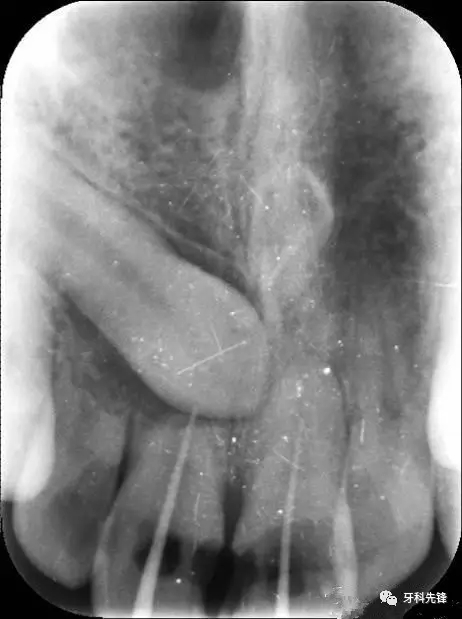

圖1.術前的根尖片影像:12、11根尖2/3壓迫吸收、11、21根管內各有一牙膠尖。